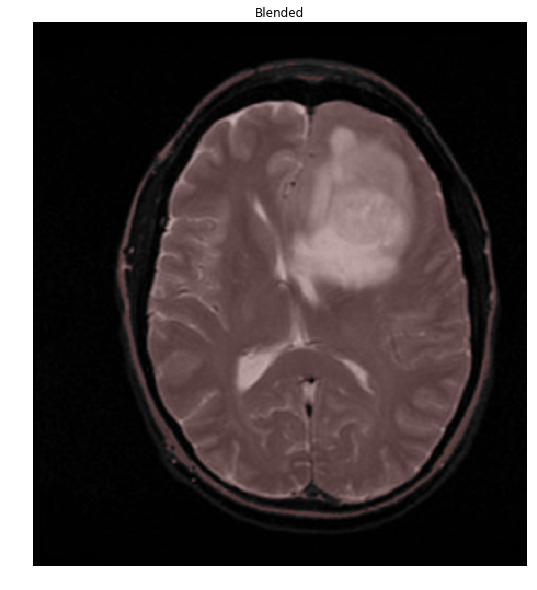

Things are easier to see if we overlay our mask onto the original image

colormask = np.zeros(img.shape, dtype=np.uint8)

colormask[thresh!=0] = np.array((0,0,255))

blended = cv2.addWeighted(img,0.7,colormask,0.1,0)

ShowImage('Blended', blended, 'bgr')